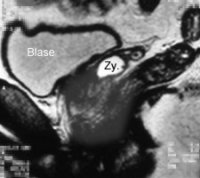

Der jüngere Erwachsene kam wegen Unterleibsschmerzen und Dysurie in Behandlung. Es fanden sich ein Harnwegsinfekt sowie eine rezidivierende Nebenhodenentzündung rechts. Trotz Antibiotikabehandlung entsprechend Keimtestung blieben die rechtsseitigen Unterleibsbeschwerden bestehen. Die Sonographie ergab Verdacht auf eine Raumforderung im rechten Samenblasen-Prostata-Bereich. Im MRT fand sich eine rechtsseitige Zyste der Samenblasen (bzw. Müller-Gang-Zyste) (Abbildung 6).

Die Nierensonographie und das Ausscheidungsurogramm ergaben eine rechtsseitige Nierenagenesie.

Eine diagnostische Punktion der Zyste (DD: Abszess, Tumor) lehnte der Patient ab. Unter weiterer antibiotischer Behandlung wurde er beschwerdefrei.